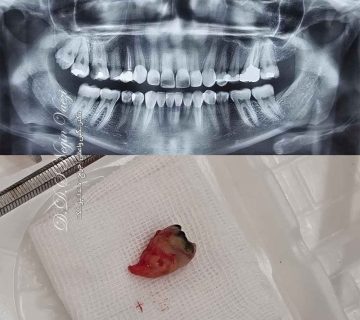

عکس جراحی دندان شکسته

عکس خارج کردن ریشه های دندانی